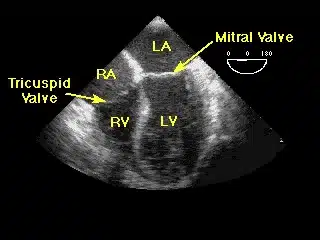

Echocardiography, also known as echo and echocardiogram, is a painless test used to diagnose heart abnormalities such as damage to the heart tissue from heart attack or poorly functioning heart valves. Echocardiography uses ultrasound waves to visualize the heart. These waves echo off the heart. They can display the shape, size and motion of the heart’s atria, ventricles and valves. Echocardiography can also show the flow of blood through the heart.

This diagnostic test is used to find probable certain cardiovascular diseases. Echocardiography is one of the most widely used tests to diagnose heart disease. Echocardiography can provide plenty of helpful data, including the size, and shape of your heart, the location and extent of any damage to the heart’s tissues and its pumping strength.